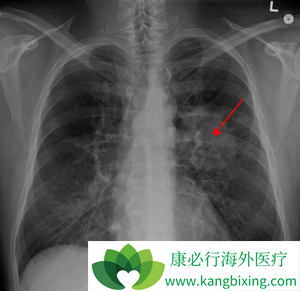

肺癌骨转移